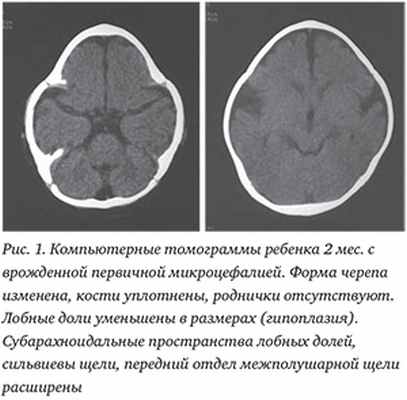

Первичная врожденная микроцефалия характеризовалась малыми размерами головы при рождении, плотными костями, наличием черепных синостозов, малыми размерами черепных родничков или их отсутствием, что согласовалось с данными литературы [2,3,10]. У 4 больных отмечались неонатальные генерализованные клонические судороги. С учетом особенностей строения родничков визуализаци.

Читайте также: